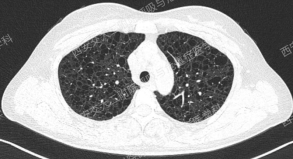

上图与Case 2比较相似,所以诊断LAM没有问题,还需进一步排查系散发型还是结节性硬化症累及。

以下2例不同患者的胸部影像改变,又分别考虑什么疾病呢?